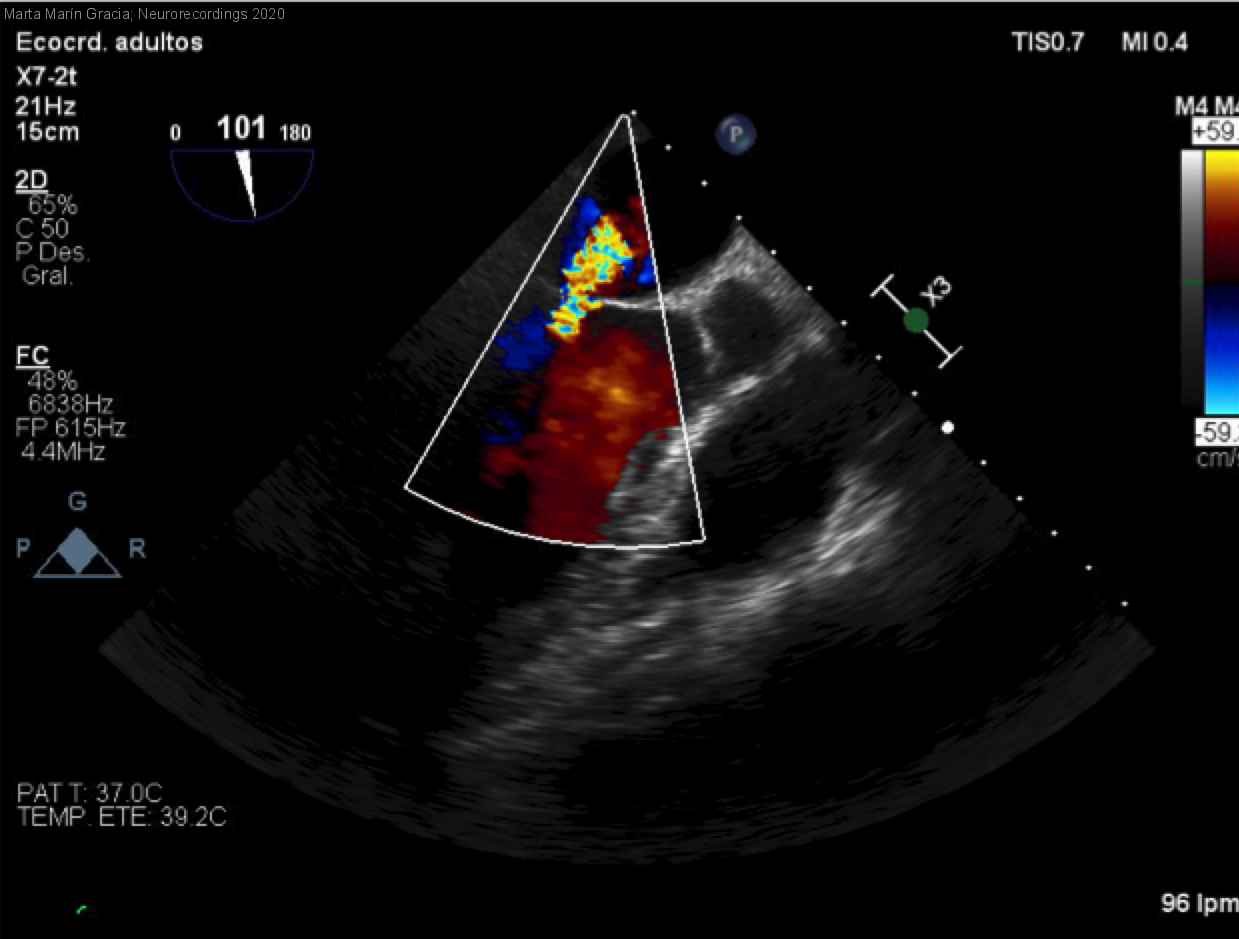

Endocarditis por Streptococcus Gallolyticus e ictus isquémico; ¿fibrinolisable?

Diagnóstico final: Ictus isquémico cardioembólico debido a endocarditis infecciosa. Hemorragia postfibrinolisis

Resumen del caso